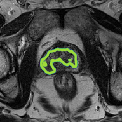

Despite their outstanding accuracy, semi-supervised segmentation methods based on deep neural networks can still yield predictions that are considered anatomically impossible by clinicians, for instance, containing holes or disconnected regions. To solve this problem, we present a Context-aware Virtual Adversarial Training (CaVAT) method for generating anatomically plausible segmentation. Unlike approaches focusing solely on accuracy, our method also considers complex topological constraints like connectivity which cannot be easily modeled in a differentiable loss function. We use adversarial training to generate examples violating the constraints, so the network can learn to avoid making such incorrect predictions on new examples, and employ the Reinforce algorithm to handle non-differentiable segmentation constraints. The proposed method offers a generic and efficient way to add any constraint on top of any segmentation network. Experiments on two clinically-relevant datasets show our method to produce segmentations that are both accurate and anatomically-plausible in terms of region connectivity.